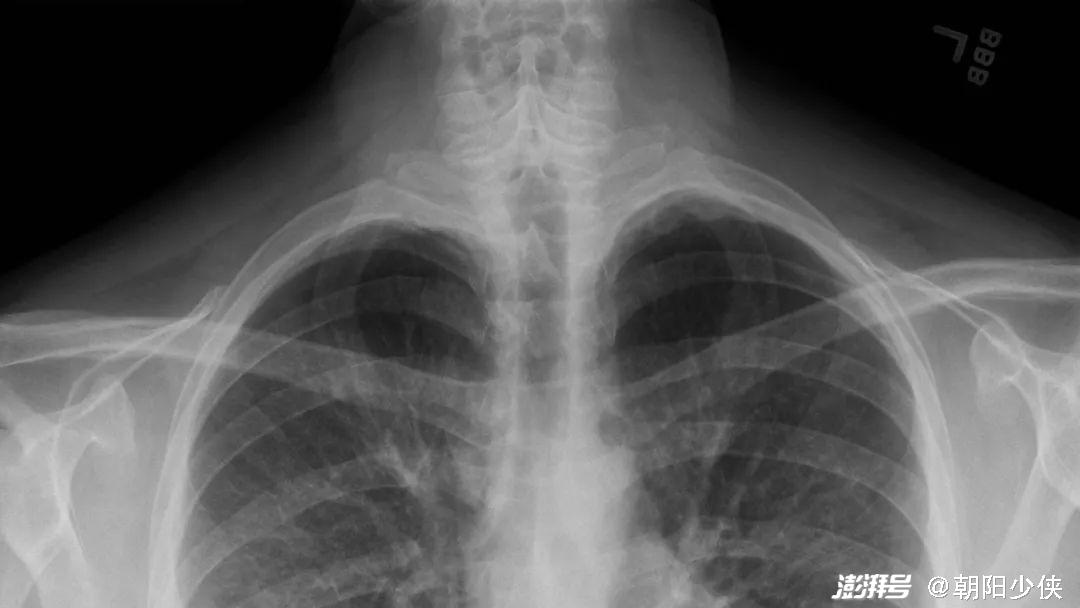

▲ 2019年9月,美国《纽约时报》曾报道美国所谓的“电子烟肺炎”,称这种疾病“很神秘”。图为“电子烟肺炎”患者的胸部X光片,这种“大白肺”与新冠患者的胸片高度相似。